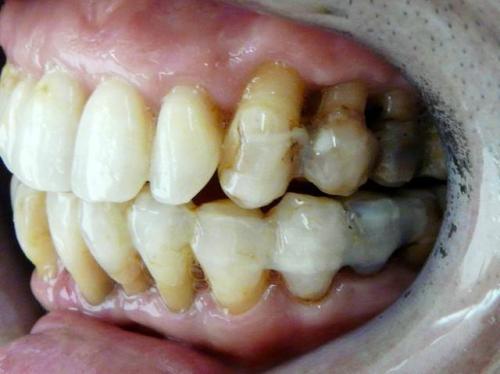

如果不清洗,随着牙菌斑在牙面上的堆积,口腔中的矿质物质就会逐渐形成白色或黄色的、粗糙的牙石。到达这一阶段,再认真的刷牙也无济于事。

人们在日常生活中,肉眼能看到的是牙石,故认为牙周炎与牙石有关。但事实上,牙石或牙面上附着的牙菌斑才是牙周病的诱发因素。而牙石只是一个局部性的刺激,进一步恶化牙周炎的病情而已。